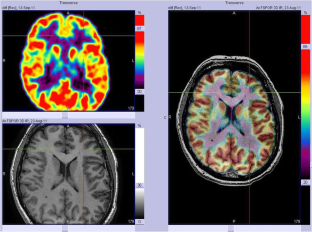

We analysed 18F-FDG PET scans from 103 consecutive patients (52 males, 7–65 years old) with histologically proven FCD2. PET and MRI data were first reviewed by visual analysis blinded to clinical information and FCD2 location. The additional value of electroclinical data and PET/MRI coregistration was assessed by comparison with pathological results and surgical outcomes.

Visual analysis of PET scans showed focal or regional hypometabolism corresponding to the FCD2 in 45 patients (44%), but the findings were doubtful or misleading in 37 patients and negative in 21. When considering electroclinical data, positive localization was obtained in 73 patients, and this increased to 85 (83%) after coregistration of PET and MRI data. Under the same conditions, MRI was positive in 61 patients (59%), doubtful in 15 and negative in 27. The additional value of PET was predominant in patients negative or doubtful on MRI, localizing the FCD2 in 35 patients (83%). Interobserver agreement correlated with the grade of hypometabolism: it was good in patients with mild to severe hypometabolism (82–95%), but moderate in those with subtle/doubtful hypometabolism (45%). The main factors influencing positive PET localization were the grade of hypometabolism and the size of the FCD2 (P < 0.0001). Misleading location (nine patients) was associated with a small FCD2 in the mesial frontal and central regions. Following limited cortical resection mainly located in extratemporal areas (mean follow-up 5.6 years), a seizure-free outcome was achieved in 94% of patients, including Engel’s class IA in 72%.

In this series, 18F-FDG PET contributed to the localization of FCD2 in 83% of patients. This high localizing value was obtained by integration of electroclinical data and PET/MRI coregistration. This approach may help improve the surgical outcome in extratemporal epilepsy, even in patients negative on MRI.